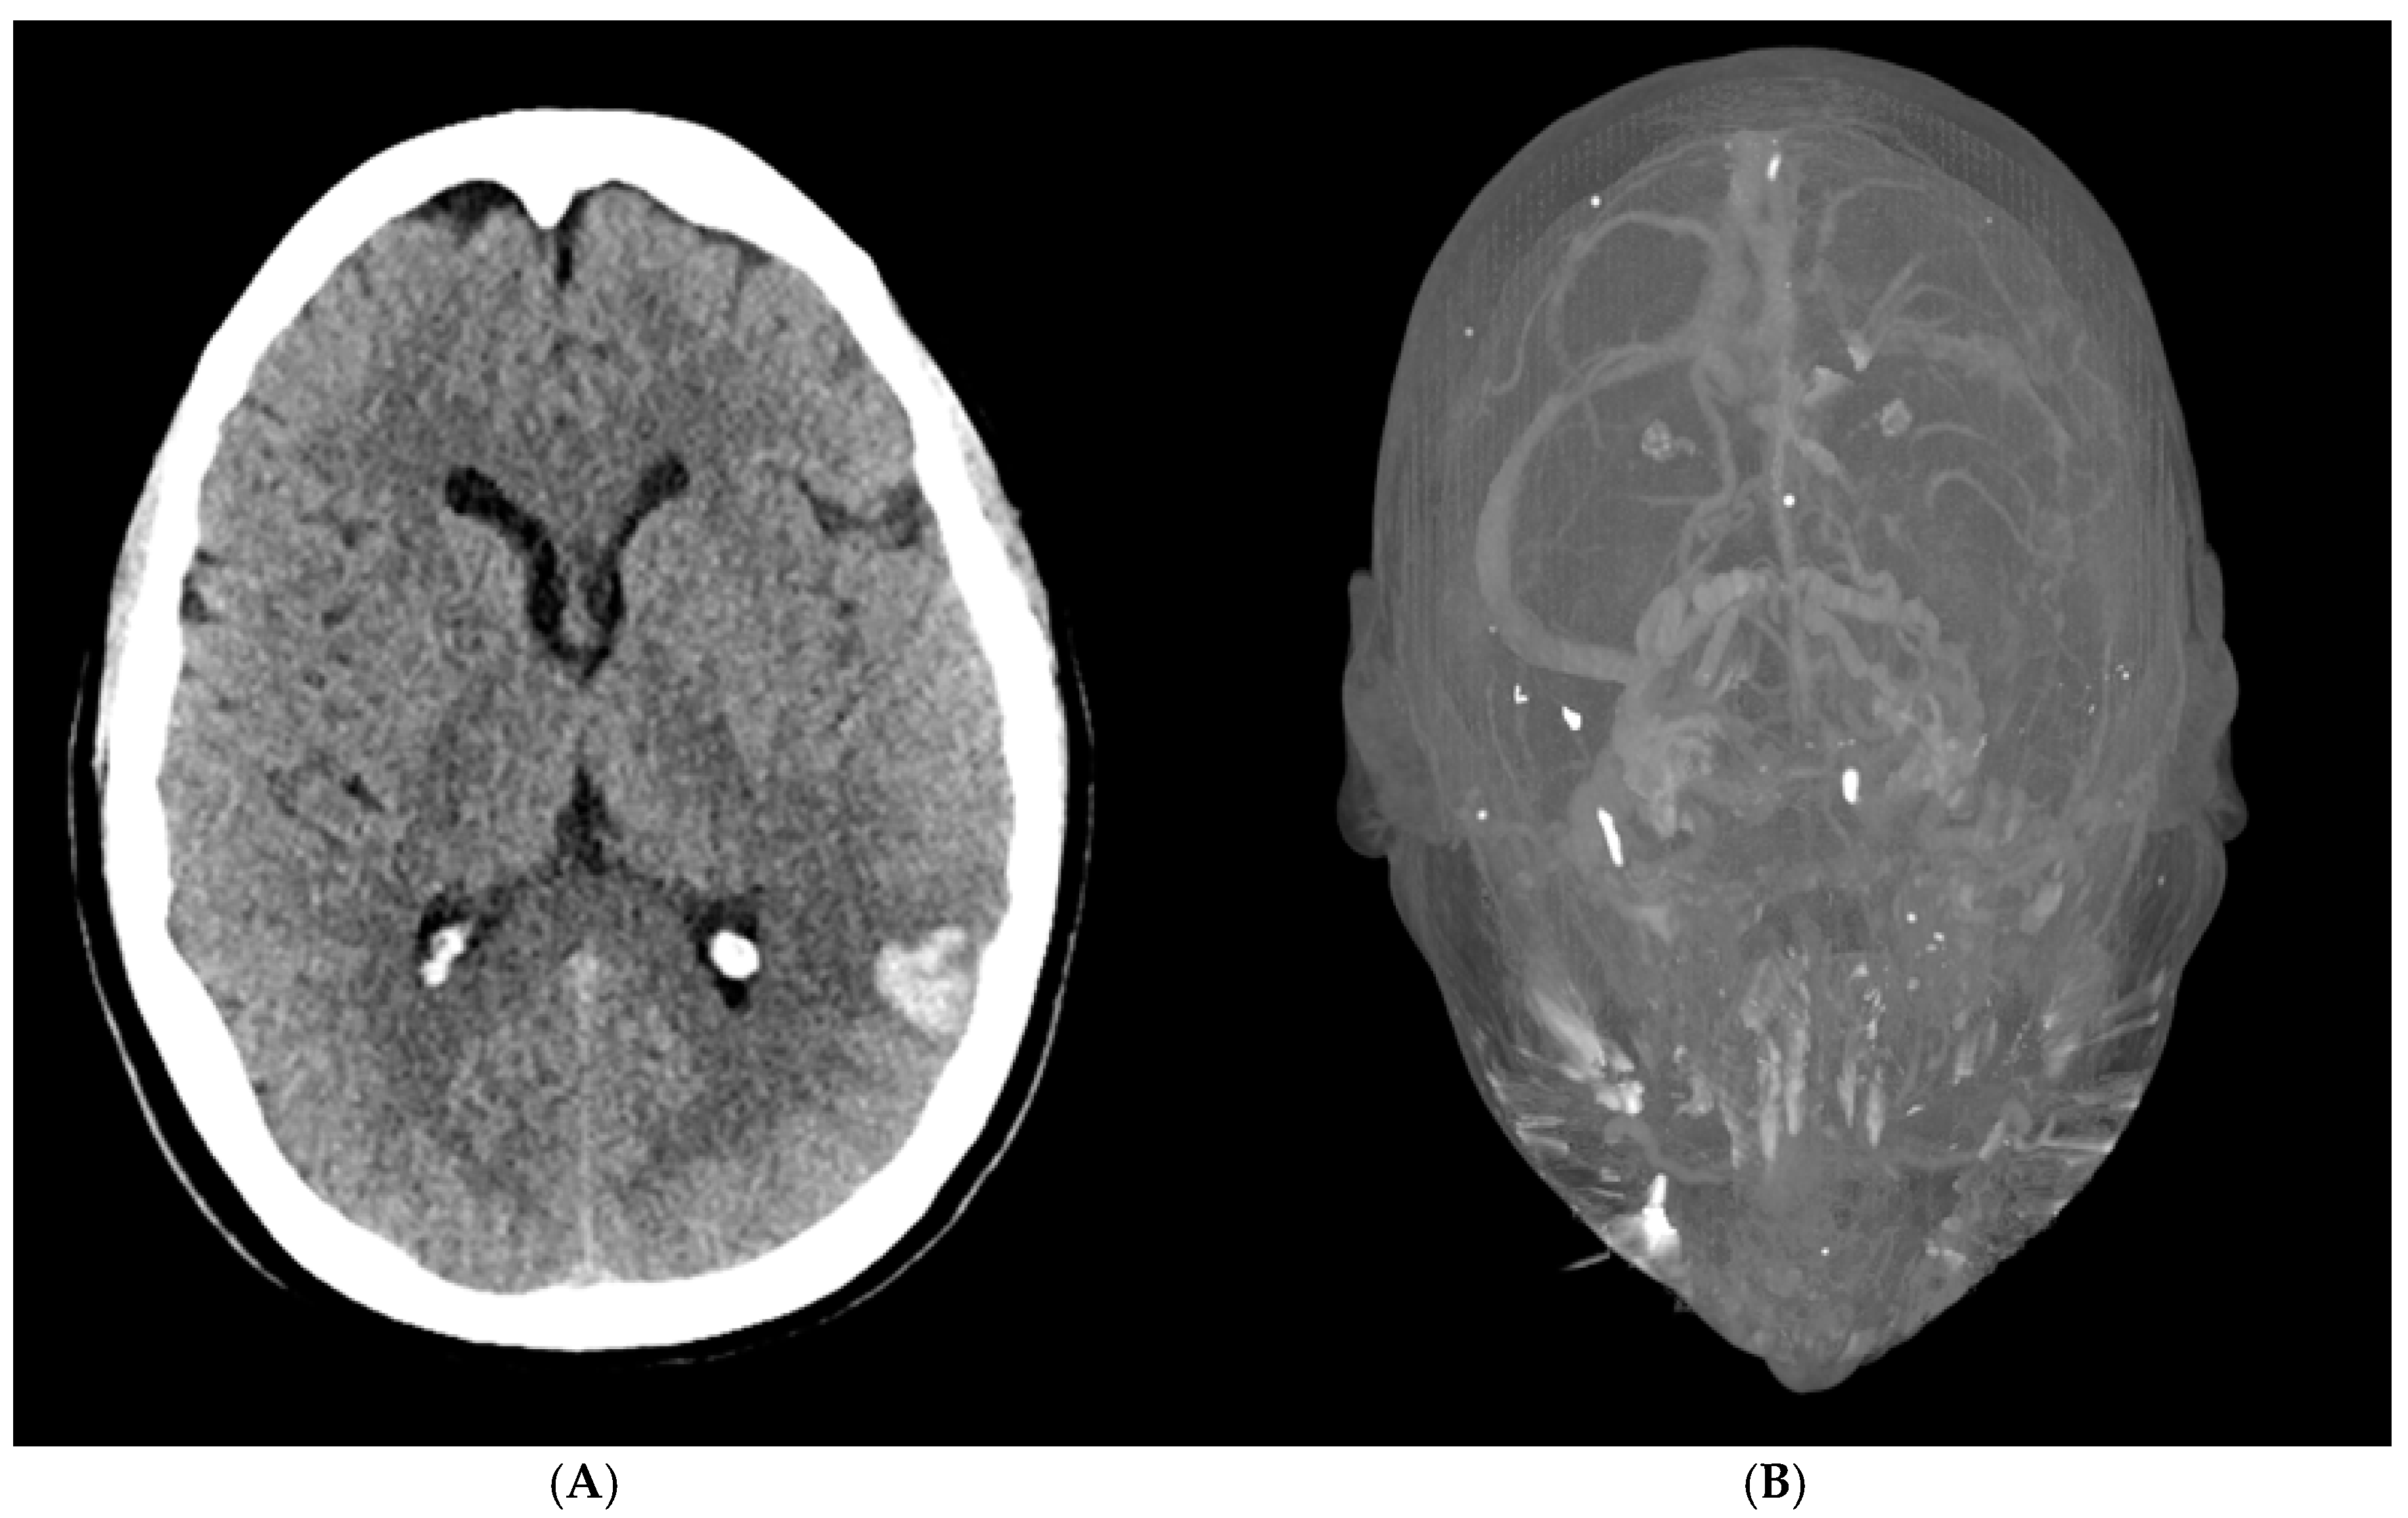

A 56-year-old woman presented to the emergency department with acute altered mental status, a headache localized to the left forehead, and aphasia. Her medical history was notable for severe osteoarthritis, for which she had undergone a left total knee replacement two weeks prior. Upon arrival, an initial brain CT revealed a 1.7 × 2.3 × 2.9 cm intraparenchymal hemorrhage in the posterior left temporal-parietal region, with mild surrounding vasogenic edema (Figure 1A). A follow-up CT venogram confirmed cerebral venous sinus thrombosis (CVST) involving the left transverse and sigmoid sinuses, as well as thrombosis of the upper left internal jugular vein (Figure 1B). These findings were consistent with hemorrhagic transformation in the setting of venous sinus thrombosis. A repeat brain CT the following day showed no significant interval changes, indicating a stable condition.

Figure 1. (A) Non-contrast CT (bottom) reveals intraparenchymal hemorrhage in the left temporoparietal region, consistent with hemorrhagic transformation due to CVST. (B) CT venography (top) shows cerebral venous sinus thrombosis (CVST) with thrombosis of the dural sinuses.